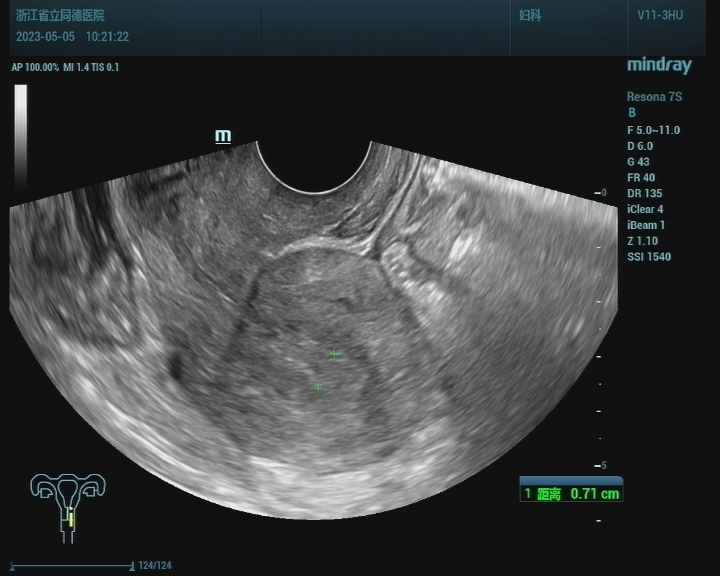

术后3月(2023.5.5)复查B超提示子宫正常大。

图1